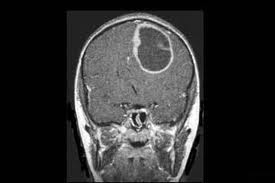

Σύμφωνα με την επίσημη ανακοίνωση η οποία θα γίνει στην Βοστώνη απο ομάδα ογκολόγων οι οποίοι μελέτησαν την ανακάλυψη του Παναγιώτη Καρδαμίτση, η καρκινογέννηση αποτελεί ψυχική πάθηση οφειλόμενη σε βλάβη του κέντρου Δ της εγκεφαλικής λειτουργίας σε συνδυασμό με καταθλιπτική προδιάθεση το οποίο έχει ώς αποτέλεσμα τον επηρεασμό της ηλεκτροχημικής λειτουργίας του.

Το κέντρο Δ αποτελεί τον εντολέα του κυτταρικού συστήματος, τών αρχών λειτουργίας, μετάλλαξης, πολλαπλασιασμού η νέκρωσης των κυττάρων με αποτέλεσμα η δυσλειτουργία του να θέτει την κυτταρική διαδικασία (κύκλο) σε ανεξέλεγκτη λειτουργικότητα.